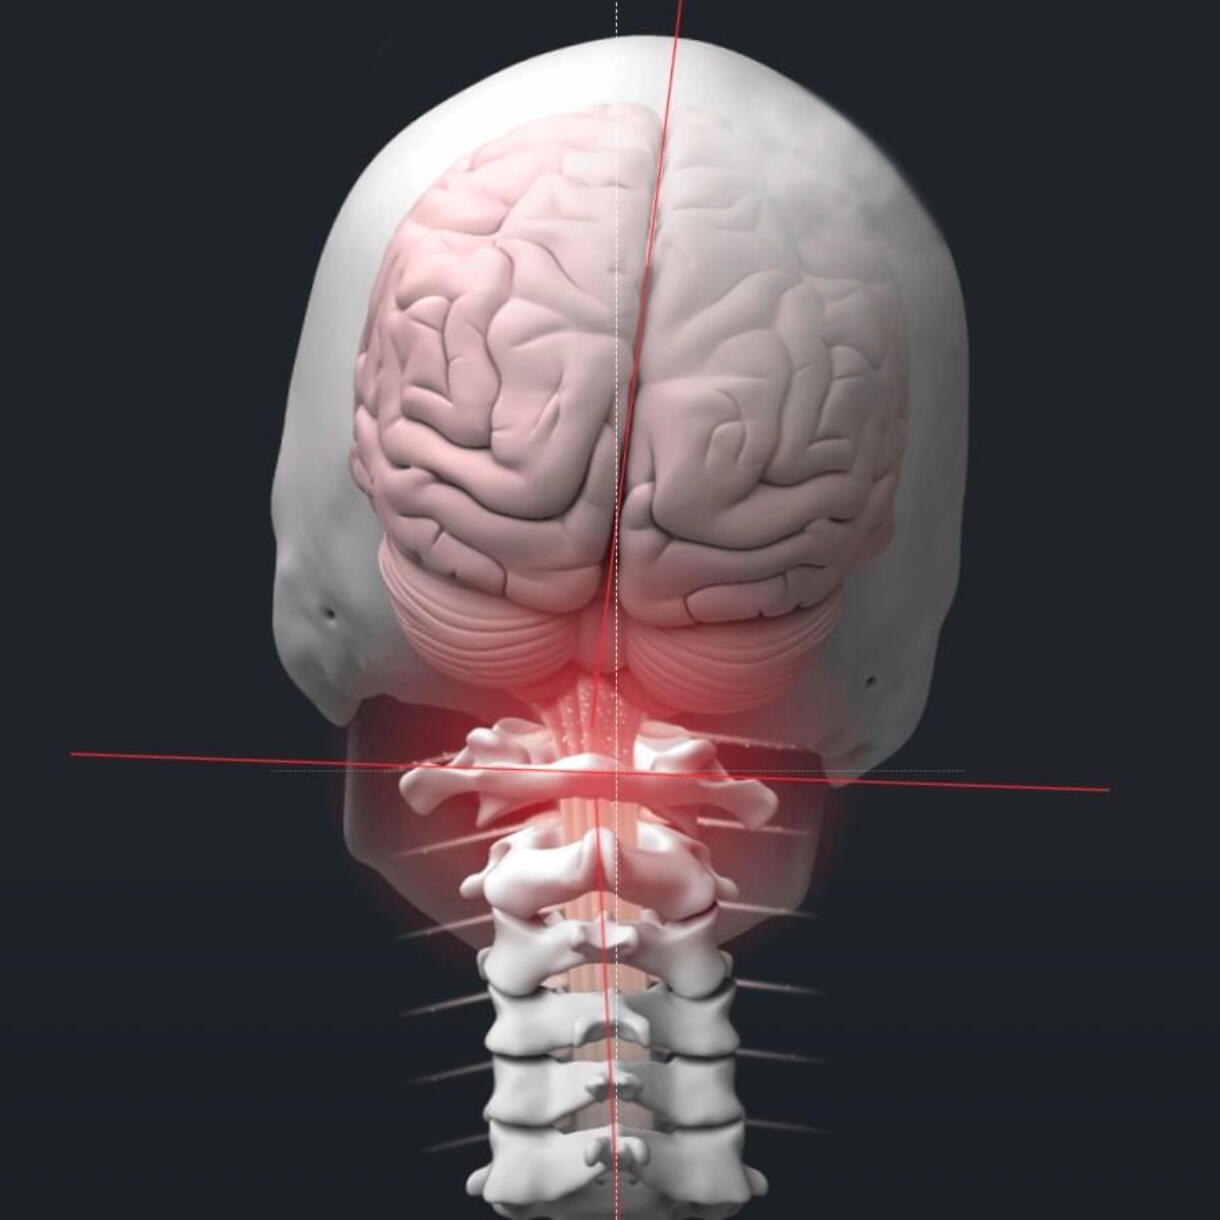

Our chiropractic care focuses on how the brain and nervous system communicate with the body. We use precise, specific adjustments, not force, to support function and healthy adaptation.This approach is gentle and safe for families, children, and athletes alike. The goal is not chasing symptoms, but helping the body change how it adapts and functions over time.